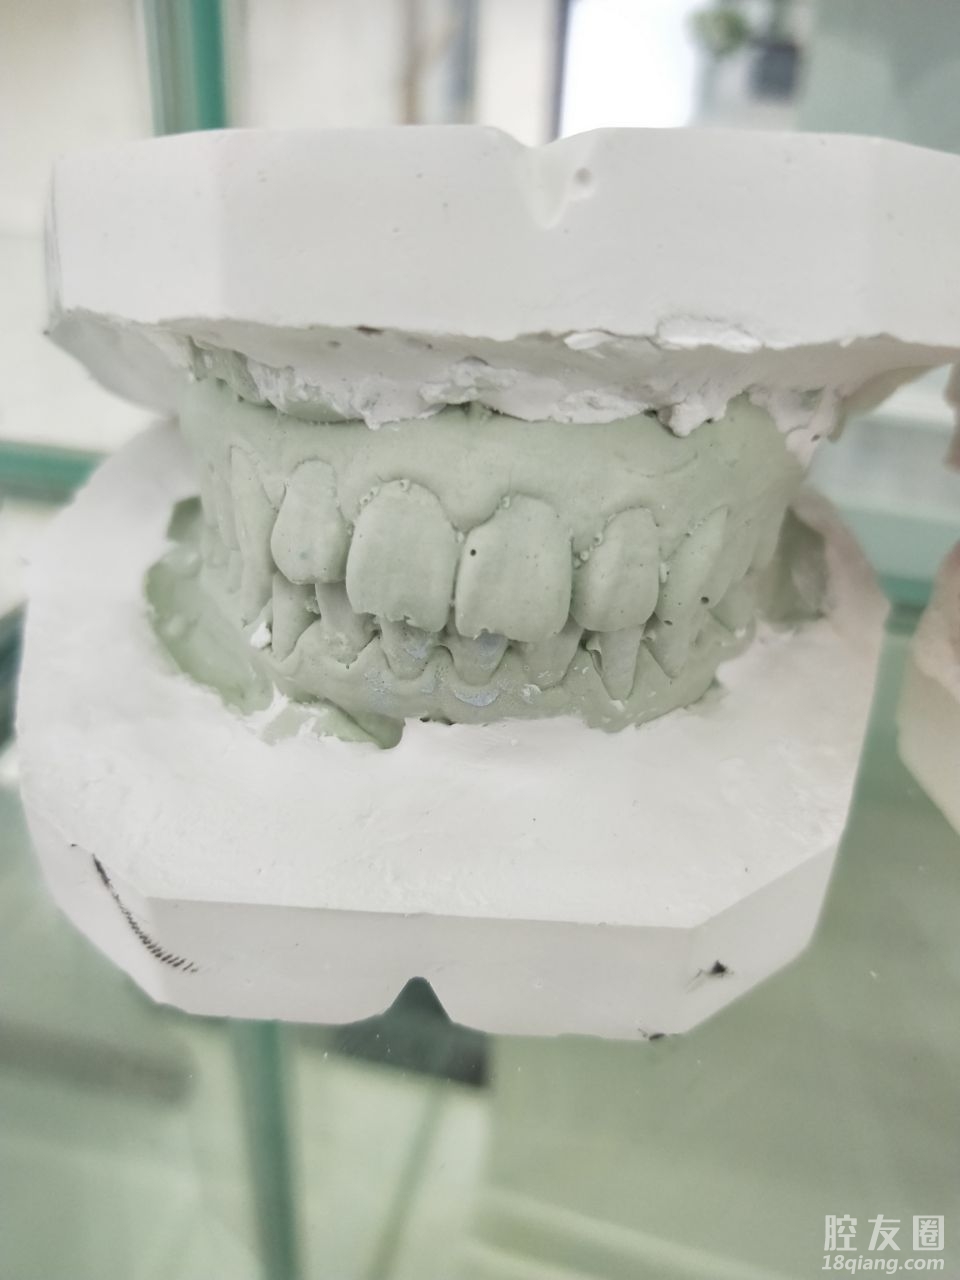

第二,价格公开透明,无推销隐形消费。小姐姐帮我做了3D口扫,设备先进,方便快捷。可以清晰实时地看到自己口腔内的状况。还问了医生整牙会不会瘦脸,医生很实在的告诉我不能,还是要结合很多因素一起看的。但是要是拔智齿导致吃不下饭确实会瘦哈哈哈哈~太可爱啦!

第三,技术专业,服务一流。口扫+拍片子+出方案,当天就很满意交了定金,希望矫正成功。